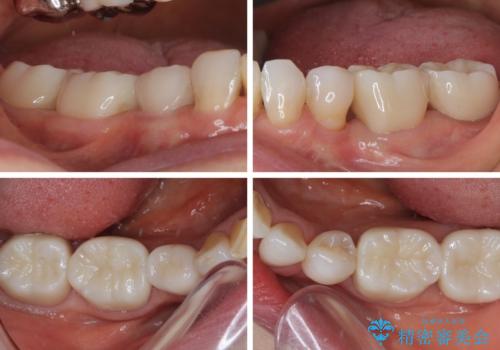

長年口を開ける度に気になっていた銀歯が一気に自然な色合いとなり、患者様には大変満足していただけました。